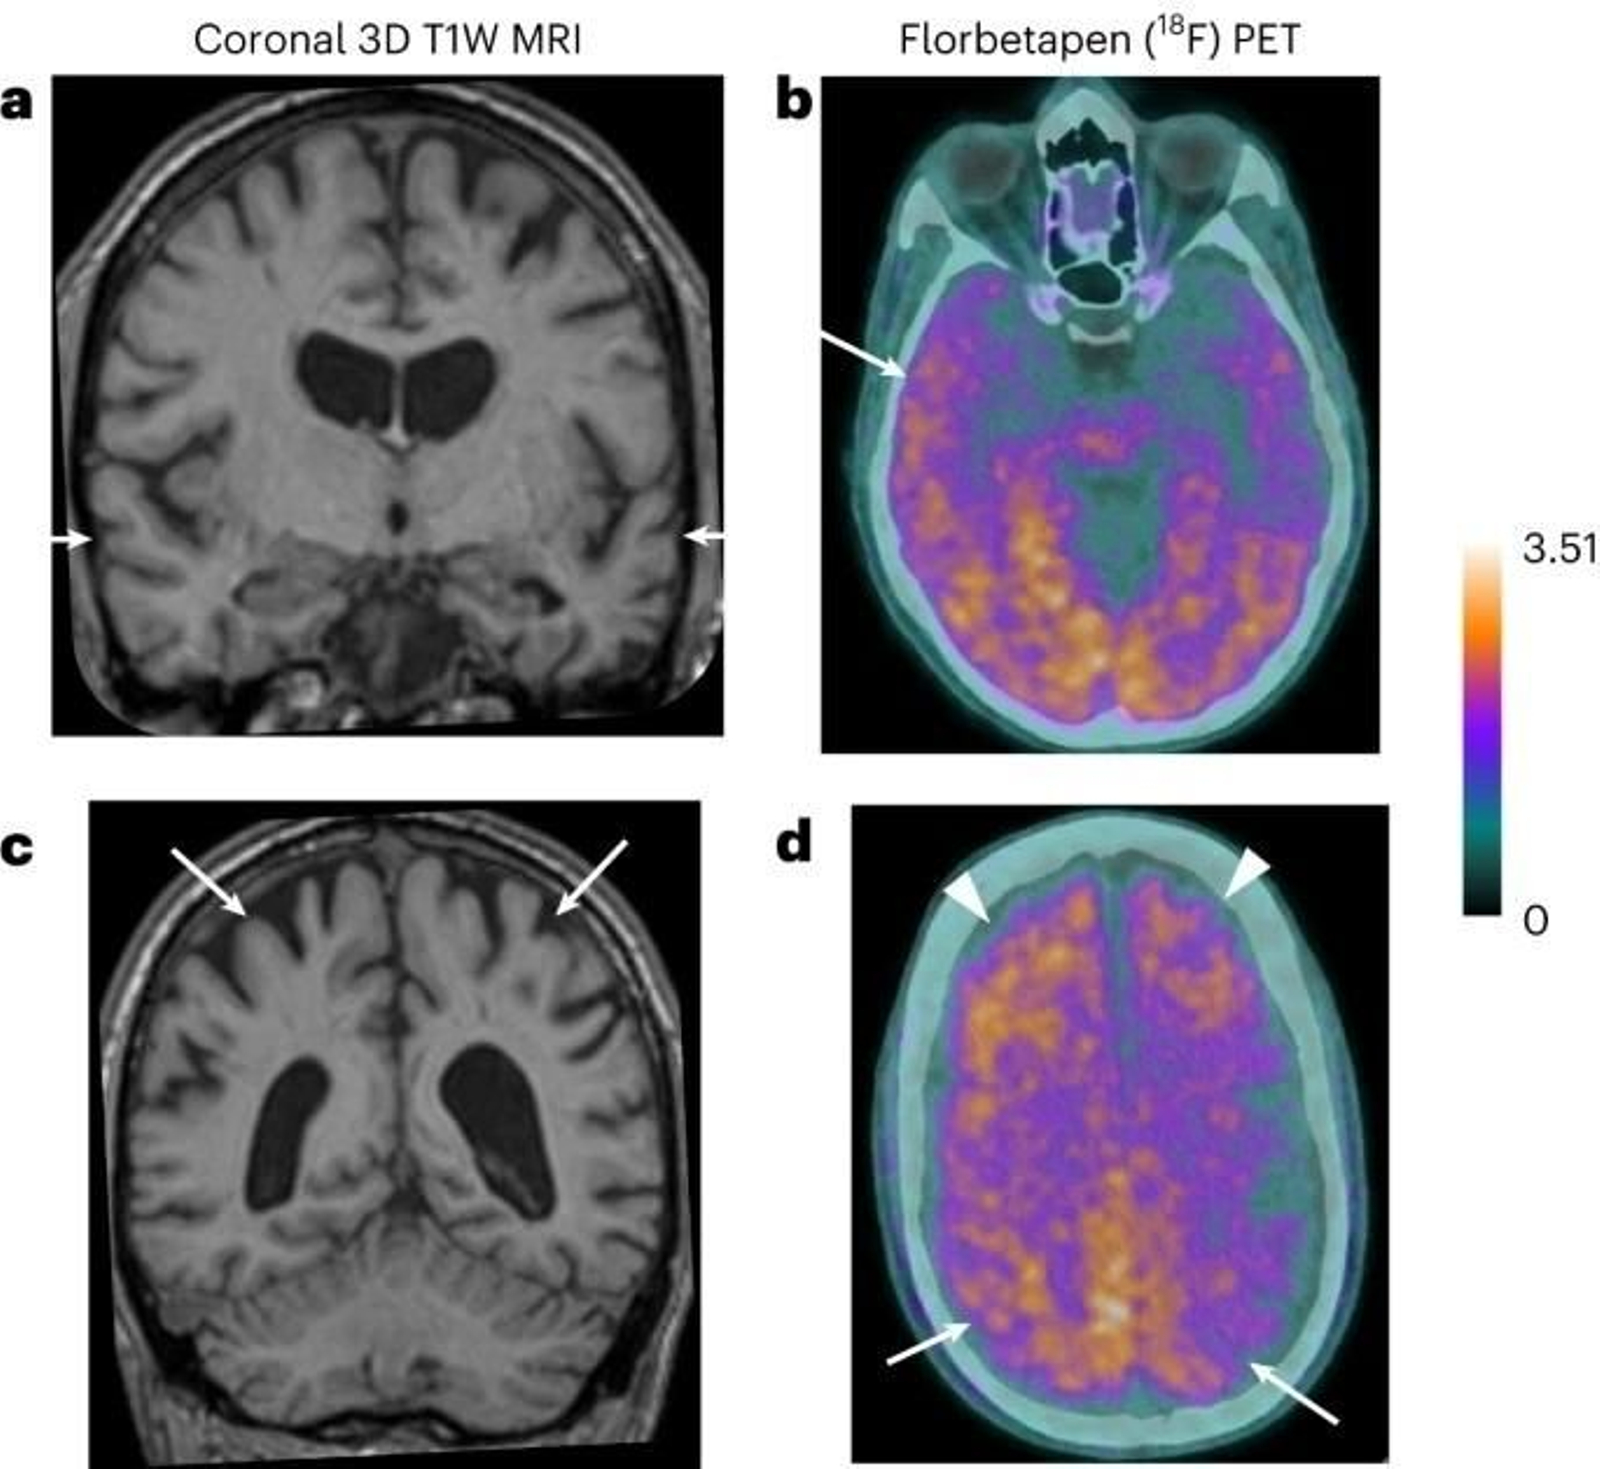

Imagen del estudio realizado para describir los primeros casos de transmisión del alzheimer

Imagen del estudio realizado para describir los primeros casos de transmisión del alzheimer / Nature.com